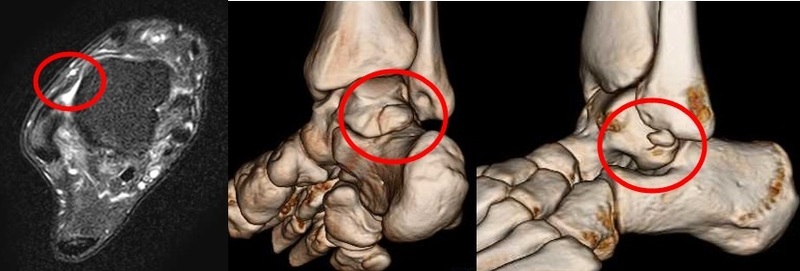

バレエダンサーやサッカー選手に多い三角骨障害(図b)や、靭帯を損傷した際に生じる外側のくるぶしの裂離骨折部(図c)の摘出もまれにおこないます。

【図a:前距腓靭帯損傷、b:三角骨、c:外果裂離骨折部の遊離体】